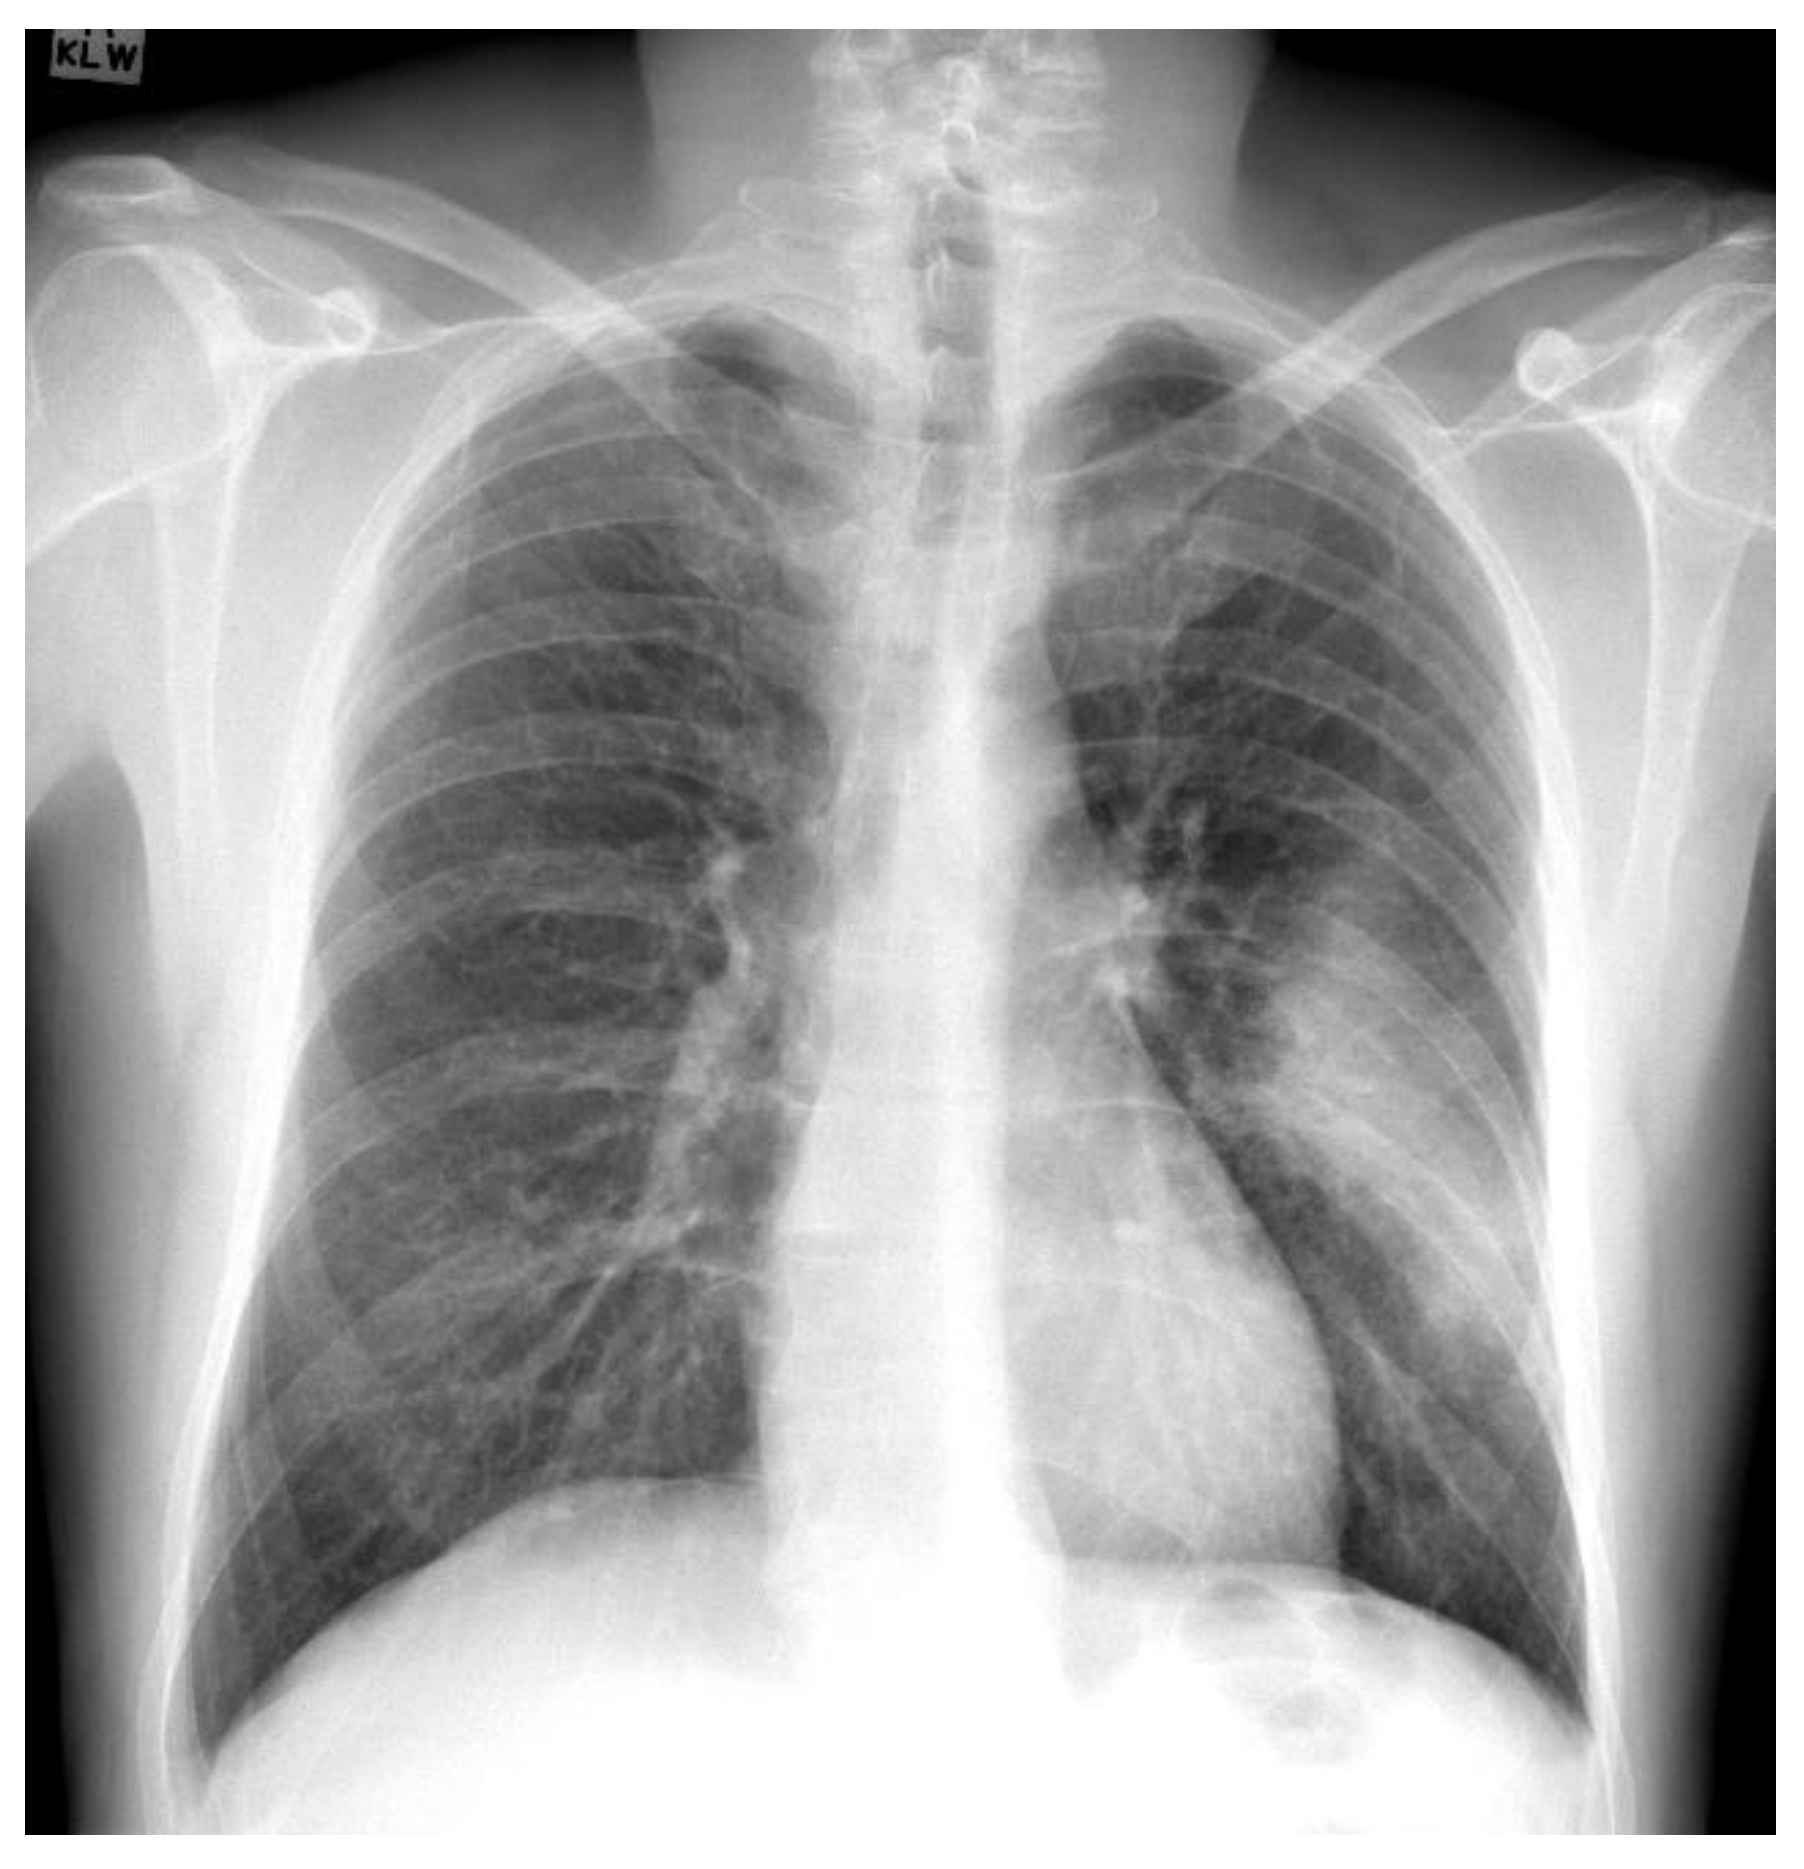

The Montgomery dataset [45,46] was marked by radiologists for tuberculosis detection and comprised of 80 chest radiographs marked as normal and 58 cases marked as tuberculosis. Similarly to the Shenzhen dataset, the lung masks marked by radiologists are available publicly. Figure 3 presents one example marked as normal and one example marked as tuberculosis from the Montgomery dataset.

Figure 3. Chest radiograph examples from the Montgomery dataset marked by radiologists: (a) normal; (b) tuberculosis.